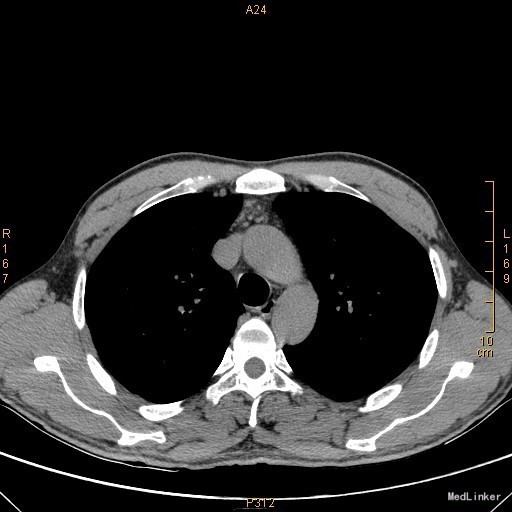

主诉:左眼睑下垂1年,加重半年。病史:患者1年前无明显诱因出现左眼睑下垂,抬起困难,伴视物重影,无言语不能、吞咽困难,无发热、头痛、恶心、呕吐、头晕、视物旋转、肢体麻木、饮水呛咳、视物模糊、肢体不自主运动、肢体抽搐、意识障碍、大小便失禁,休息后缓解,未予重视,半年来上述症状反复加重,10余天前至当地医院就诊,查新斯的明试验阳性,遂至我院神经内科就诊,胸部CT示:1、右肺尖钙化结节;2、胸腺增生。为了进一步治疗门诊拟“重症肌无力”收住我科。患者自起病以来,无发热、咳嗽、尿频、尿急、腹泻,无心悸、胸闷等,精神、食欲、睡眠好,体重无明显变化。

查体:左侧眼睑下垂,右侧眼裂宽10mm,左侧眼裂宽5mm。肺部查体未见异常。 辅查:新斯的明试验阳性。胸部CT示1、右肺尖钙化结节;2、胸腺增生。

该患者诊断“1.重症肌无力,眼肌型;2.右上肺钙化结节”明确,重症肌无力合并胸腺增生或胸腺瘤,有手术指征,我们为患者行胸腔镜下胸腺扩大切除术+右肺上叶楔形切除术。术后病理示:右上肺结节呈干酪样坏死,考虑结核。胸腺及纵隔脂肪均见淋巴增生。术后效果明显,患者左侧眼睑下垂较前好转,右侧眼裂宽10mm,左侧眼裂宽8mm,视物重影症状消失。